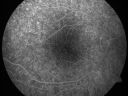

Pigmented Maculae - Mother and Daughter - Normal Visual Acuity503 viewsMothers macular photos     (0 votes)

Pigmented Maculae - Mother and Daughter - Normal Visual Acuity545 viewsMothers macular photos     (0 votes)

Pigmented Maculae - Mother and Daughter - Normal Visual Acuity565 viewsMothers macular photos     (0 votes)

Pigmented Maculae - Mother and Daughter - Normal Visual Acuity646 viewsMothers macular photos     (0 votes)

I checked the mother’s eyes and they look exactly the same.